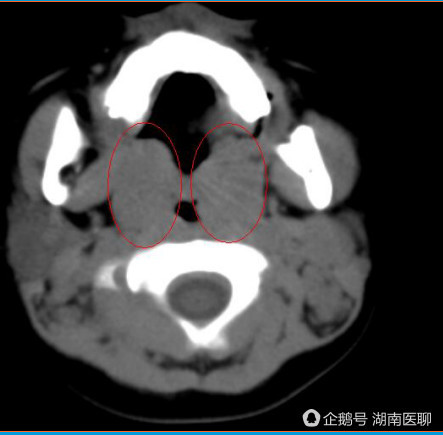

9岁的豆豆还是个懵懂的孩子,但是她的乳房从两年前就开始发育了,胸围接近少女的脑积水,视中隔发育不全等